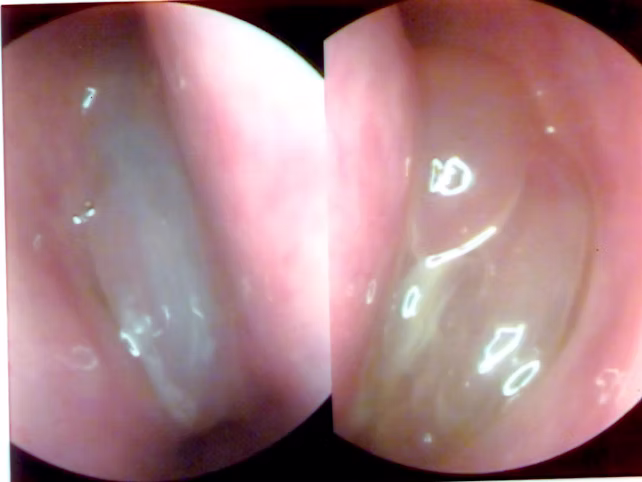

Poliposis Nasal

La poliposis nasal o pólipos nasales es una enfermedad que afecta el interior de la nariz (y los senos paranasales) por el crecimiento de tumores benignos que obstruyen la respiración. Es una forma especial de sinusitis (llamada «sinusitis polipoidea»)